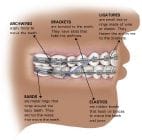

[/fusion_tab][fusion_tab title=”Aparate fixe: Aparatul ortodontic metalic” icon=””]Aparatul ortodontic metalic este cel mai des intalnit tip de aparat dentar, iar noile tehnologii au facut ca purtarea aparatului sa fie mult mai confortabila azi decat a fost anii trecuti. Componenetele aparatului dentar sunt facute din otel de inalta calitate. Aveti optiunea de a adauga elasice colorate pentru un design mai vesel si mai unic, cerinta intalnita mai ales la copii. Deoarece este foarte simplu sa schimbi aceste culori aparatul se poate personaliza la fiecare vizita la ortodont.

[/fusion_tab][fusion_tab title=”Aparate fixe: Aparatul ortodontic metalic” icon=””]Aparatul ortodontic metalic este cel mai des intalnit tip de aparat dentar, iar noile tehnologii au facut ca purtarea aparatului sa fie mult mai confortabila azi decat a fost anii trecuti. Componenetele aparatului dentar sunt facute din otel de inalta calitate. Aveti optiunea de a adauga elasice colorate pentru un design mai vesel si mai unic, cerinta intalnita mai ales la copii. Deoarece este foarte simplu sa schimbi aceste culori aparatul se poate personaliza la fiecare vizita la ortodont.

[/fusion_tab][fusion_tab title=”Aparare fixe: Aparatul ortodontic ceramic” icon=””]Aparatele ortodontice din ceramica sunt o alternativa pentru cei care nu v-or ca aparatul sa fie vizibil asa mult. Ca si aparatele dentare metalice, aparatele ortodontice ceramice sunt foarte confortabile si foarte eficiente in alinierea dintilor.

Bracketurile ceramice sunt facute dintr-un material transparent, motiv pentru care vizibilitatea lui pe dinte devine mult mai mica. In general pretul pentru un aparat ortodontic ceramic este mai mare decat pretul pentru cel metalic motiv pentru care este cerut mai ales in situatii in care se doreste ascunderea purtarii unui altfel de aparat, adica de catre tineri si la adulti.